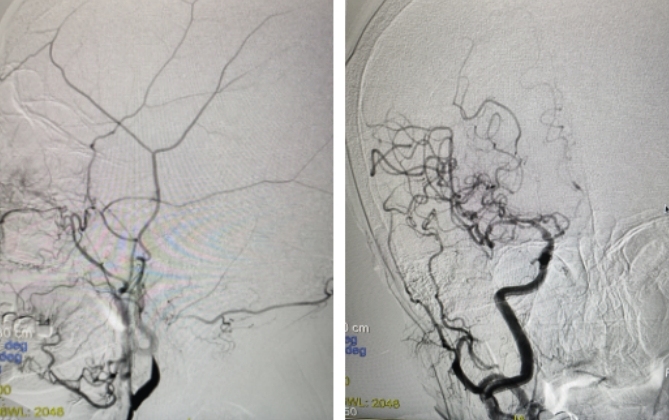

▲老人术前术后血流对比

因老人家症状进行性加重且已出现意识改变,综合考虑为大动脉闭塞导致大面积脑梗死,不进一步积极治疗预后极差。医院卒中中心脑血管介入医生紧急会诊,向家属告知病情并沟通后,决定立即桥接行血管内介入治疗。介入团队半小时内全部到位,立即为老人实施介入手术,历时1个多小时,成功开通了徐奶奶堵塞的脑部血管,血流完全恢复。术后送入ICU进行密切监护治疗。

“徐奶奶患有房颤、心源性栓塞,导致整个颈内动脉闭塞,血栓负荷非常大,90多岁老人能够得到有效救治并在短时间内迅速恢复,在国际上也较为罕见。”刘叶辉主任表示,此例患者高龄且有多种基础疾病,加上血管特别弯曲,因此手术风险和难度较大,但所幸送医及时,家属积极配合,卒中团队通力协作,没有错过最佳溶栓和取栓的时机,救治非常成功。